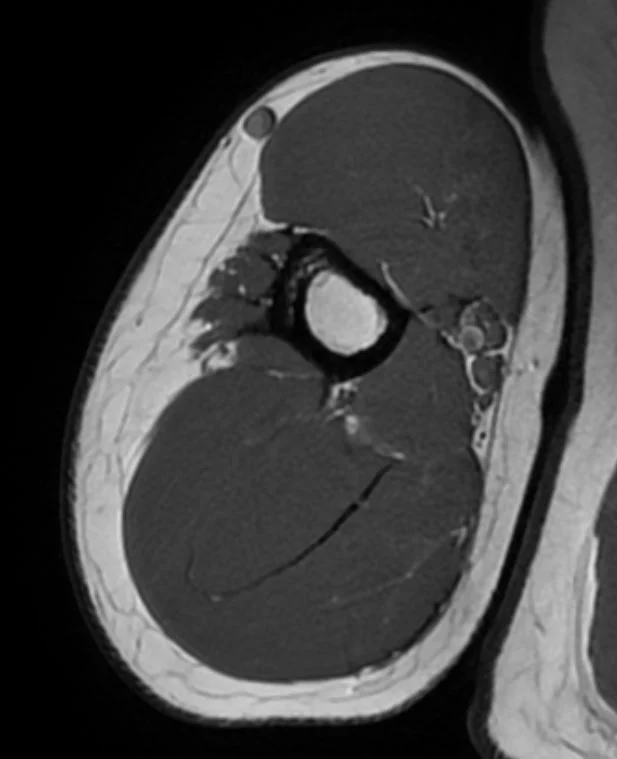

En MR-scanning af over- eller underarmen er en avanceret, non-invasiv undersøgelse, der skaber ekstremt detaljerede billeder af alle armens strukturer. Ved hjælp af kraftige magnetfelter og radiobølger kan vi visualisere:

- Knogler og knoglemarv

- Muskler og deres sener

- Nervebaner gennem armen

- Blodkar og deres forløb

- Bindevæv og fascier

- Eventuelle tumorer eller cyster

MR-scanning er særligt værdifuld for armregionen, da den visualiserer både knogler og bløddele med høj detaljeringsgrad, hvilket muliggør præcis diagnosticering af mange tilstande som ikke altid kan ses på røntgen.

Eksempler på MR Scanninger